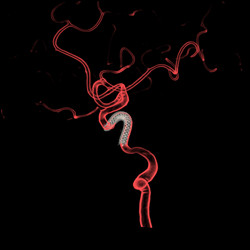

▲密网支架在血管中的展示(白色部位),

用于治疗未破裂的大型宽颈动脉瘤。